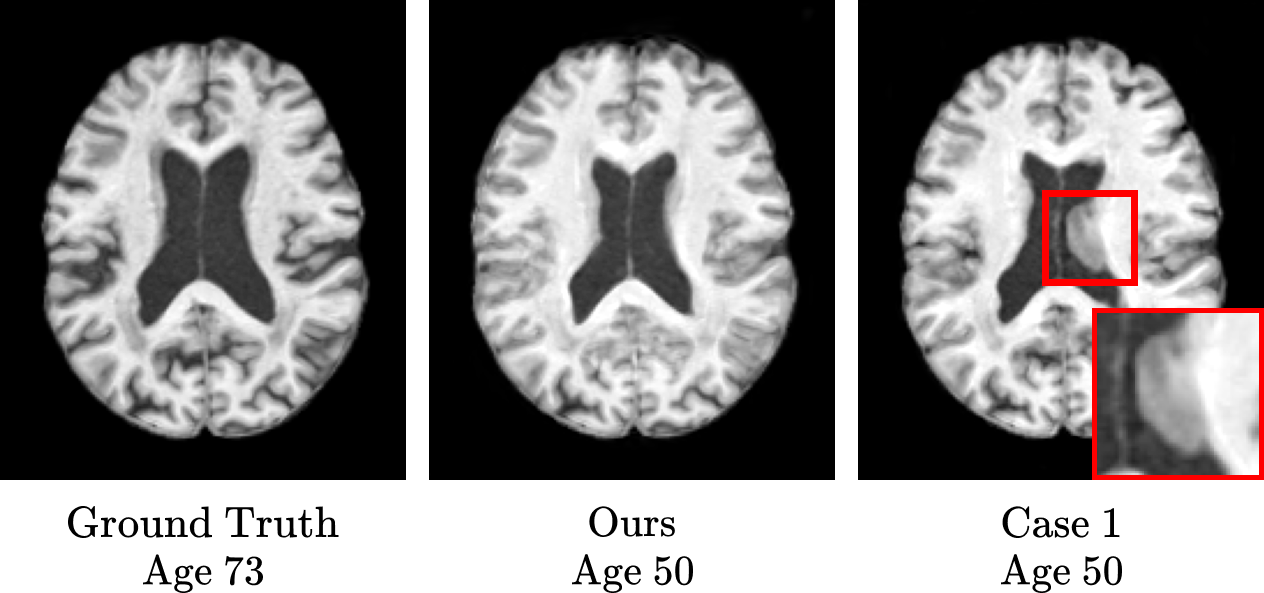

Furthermore, we conducted a series of ablation studies to verify the efficacy of specific components within our proposed method, as shown in Table 2. Case 1 examines the impact of omitting the identity-extracting loss, thereby assessing its role in enhancing model performance. Cases 2 and 3 also explore the effects of removing the cosine similarity loss and the orthogonality loss from the identity-extracting loss, respectively. In Case 4, we investigate the significance of our conditioning mechanism within the discriminator by substituting it with a conventional cGAN Mirza and Osindero (2014) approach. We observed that Case 1, which lacked all components of the identity-extracting scheme, demonstrated the lowest performance across all evaluation metrics. The results of Cases 2 and 3 also showed inferior scores compared to our complete model. The outcomes of Case 4 reveal the effectiveness of our proposed conditioning mechanism within the discriminator. We depicted a qualitative result through the ablation study, as shown in Fig. 8. In the figure, it is evident that Case 1 struggles to maintain the structural identity of the ventricles, leading to undesirable shrinkage in areas that should remain unchanged (see red boxes). Consequently, we posit that these findings provide compelling evidence of the efficacy of our proposed IdenBAT in preserving the inherent identity while accurately converting ages to the desired target ages.